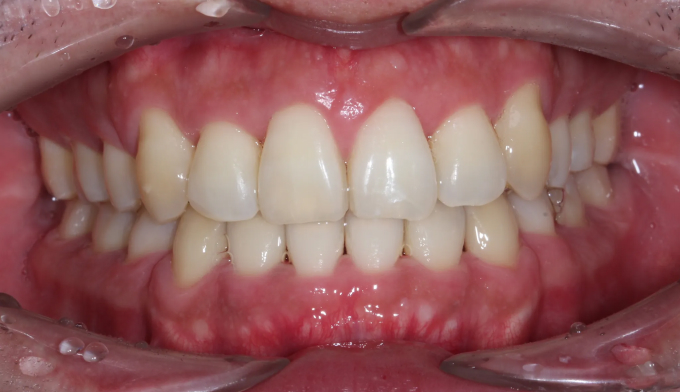

주걱턱과 돌출입, 그리고 덧니를 한꺼번에 가지고 있는 경우입니다. 이 모두를 해결하기 위해서는 필요한 공간의 양이 많기 때문에 성인에서는 작은어금니 발치가 대부분 필요합니다.

교정치료를 통해 치열이 고르게 된것은 물론, 주걱턱과 돌출입이 개선되면서 입술 모양이 보다 더 자연스러워지고 안모가 개선되었습니다.

총 교정치료는 21개월입니다.